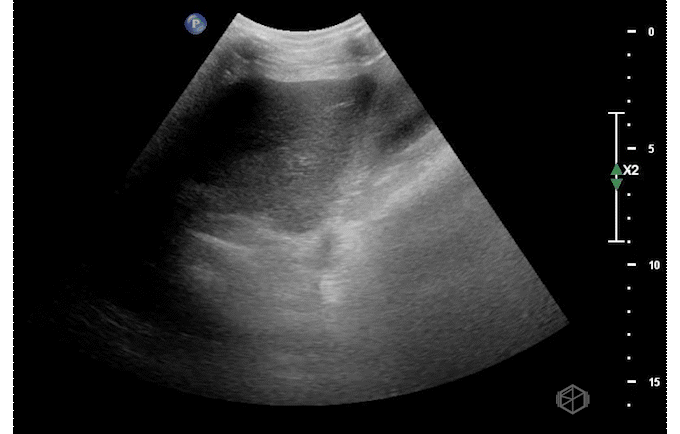

Ultrasound of the right upper quadrant demonstrated the below:

This ultrasound demonstrates a dilated common bile duct with mild gallbladder wall thickening.

• Finding the common bile duct is often difficult for novice sonographers. The common bile duct lies on top of the portal vein in long orientation making a “double barrel” type configuration as seen above. Color doppler may be used to determine the duct as there should be no flow. This is often easier to identify than the “Mickey Mouse” in short orientation.

• Due to the difficulty in determining the difference between the common hepatic duct and the common bile duct, some prefer to just call this structure the common duct (504652).

• If the labs are normal and there is no gallbladder wall thickening, pericholecystic fluid, or sonographic Murphy’s — there is little utility in finding the CBD (29162442).

• The CBD is measured inner to inner. There are various average sizes and no standard cut off but a common rule of thumb is that a dilated common bile duct is considered >4mm, increasing by 1 every decade at 50 and after. So a 70-year-old can have up to a 7mm sized CBD (14510259).

• Later studies have questioned this, however it is still considered a rule of thumb (28668951). In general, the CBD should remain under 6-7mm which is commonly accepted range for normal (11065260).